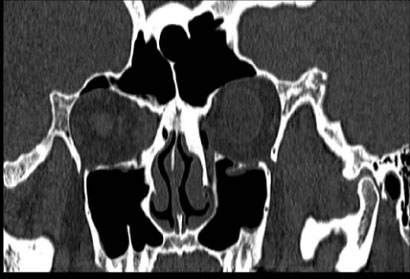

副鼻窦多平面重建: